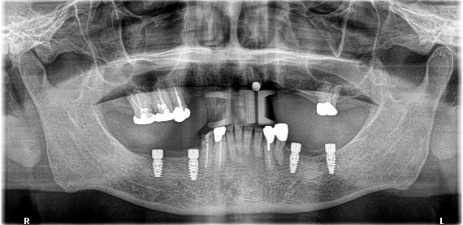

Before

▼初診時に使用していた部分入れ歯を装着したところ

▼インプラント埋入前

After

▼インプラント埋入後